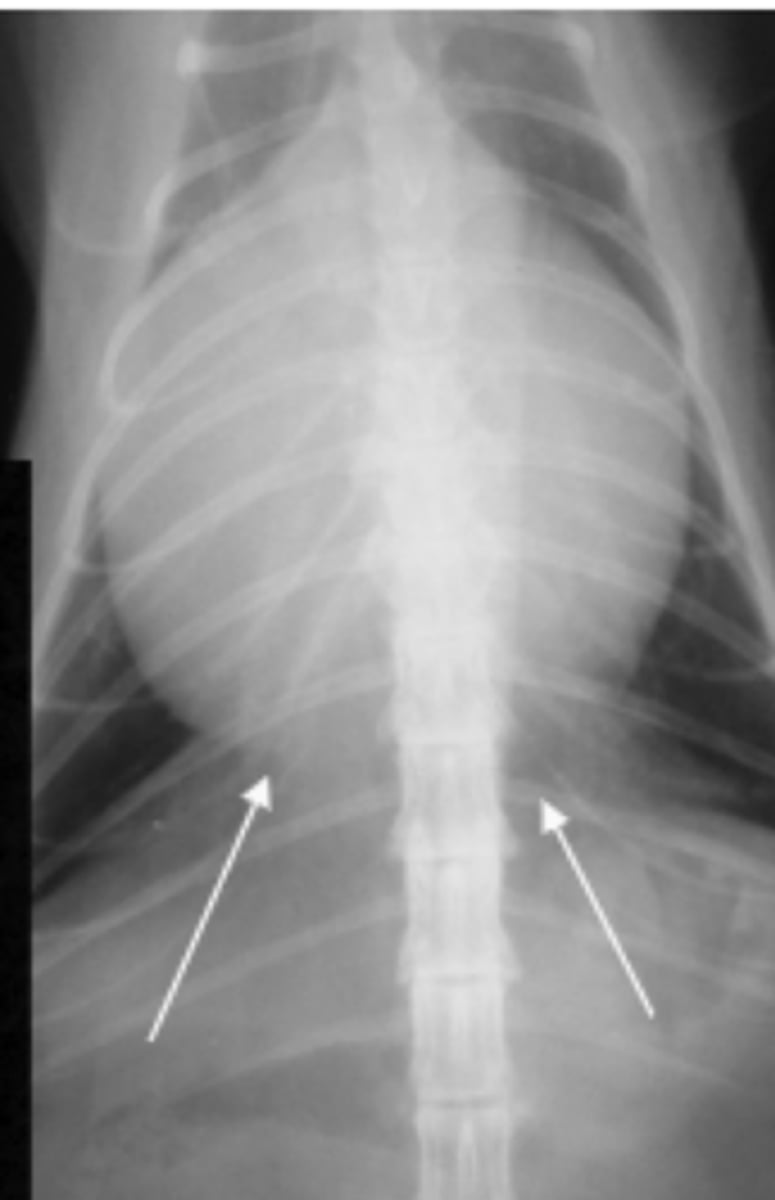

neumomediastino

patología: